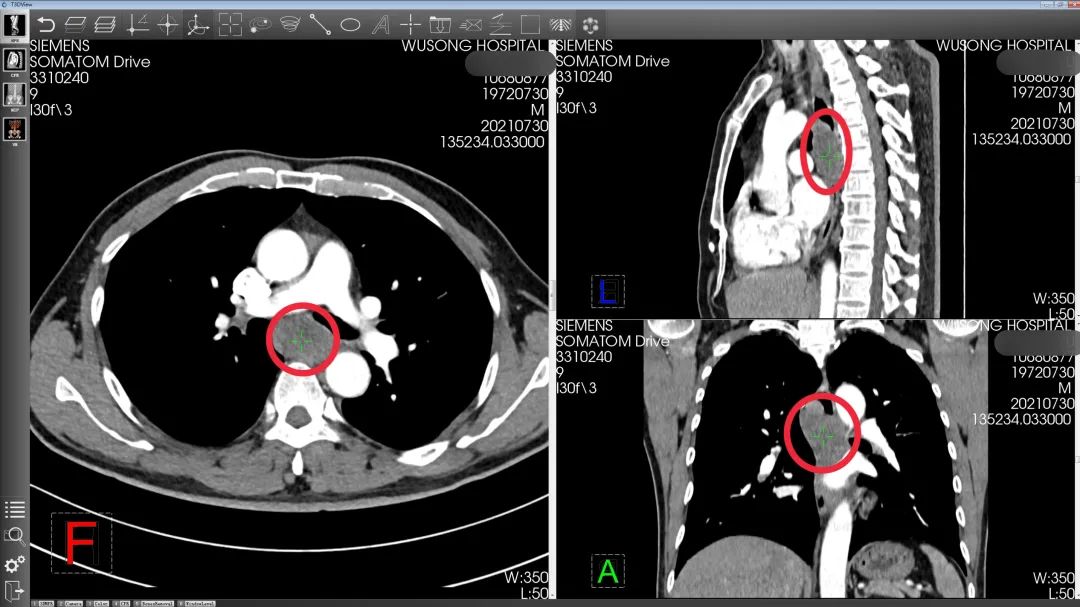

孙先生的CT影像资料(红圈内为肿瘤)

在周平红教授的指导下,吴淞医院内镜中心为孙先生制定了详细的手术方案,计划采用内镜经黏膜下隧道肿瘤切除术(STER)切除肿瘤,不用开胸,也不用切除食管。